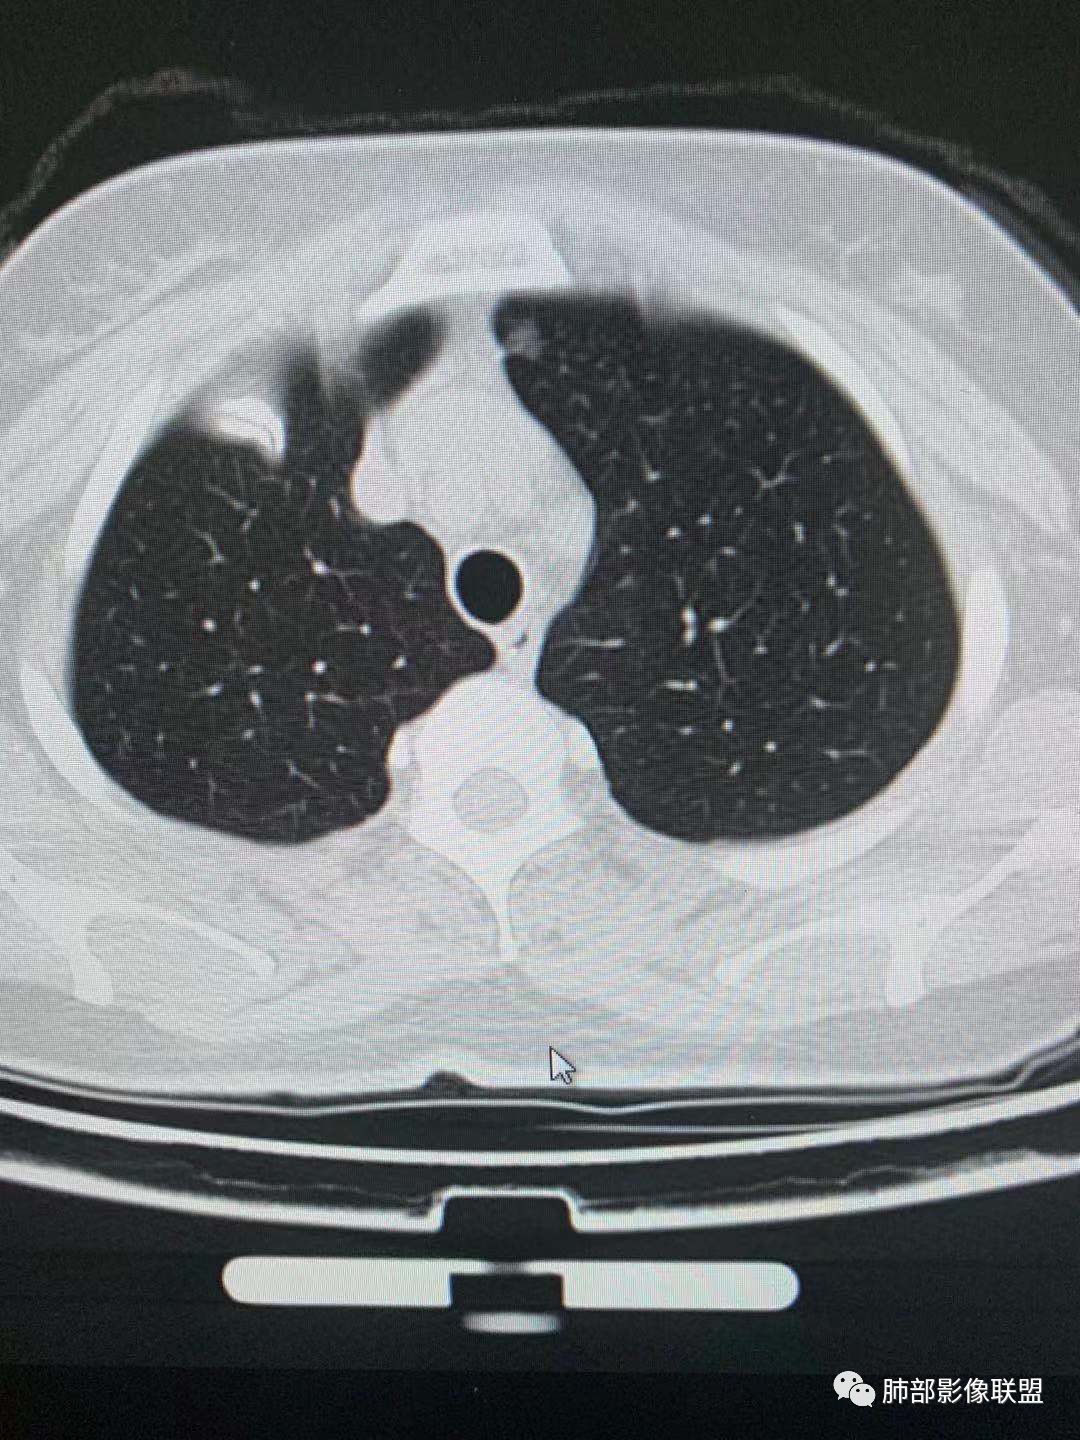

一.尖后段高密度大结节:

1.左肺上叶尖后段较大类圆形实性密度结节影,密度均匀,中等程度强化。

2.实性密度区边缘相当清楚,表面欠光整,偶见毛刺、棘突和旁出血管结构,未见典型的深分叶及邻近胸膜凹陷。

3.可疑支气管进入受阻。可惜缺乏连贯图像或冠矢状位以资判断。

4.病灶与胸膜之间有连线,邻近段支气管及肺血管整体后移,提示病灶还是有一定收缩性。

如上,单就这实性结节,硬化性肺细胞瘤(PSP)和腺癌似乎都能够解释,形态太规整了一些。

5.病灶周围见边界清楚的磨玻璃影,有点醒目,有点意外!

这是无论如何不能忽视的征象!

这点强烈提示,要么整个病灶恶性(腺癌),要么良性病灶旁滋生恶性病灶。

两年前左上肺的病灶什么位置,什么模样,是否相关?我们不得而知。